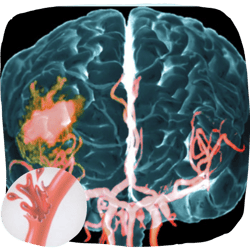

What is a Brain Aneurysm?

A brain aneurysm is a bulge or ballooning in a blood vessel in the brain. A ruptured aneurysm can cause a stroke and requires immediate medical attention.

When Aneurysms Rupture, Strokes Follow

A ruptured brain aneurysm is often the trigger for a stroke — one of the deadliest medical emergencies. Strokes happen in two main ways: when blood flow is blocked, or when a vessel bursts and floods the brain with blood. Both are catastrophic, and both demand immediate care.